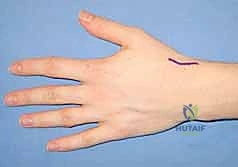

The surgical execution of a distal scaphoid pole excision can be performed via a dorsal or a volar approach. The choice often depends on the exact location of the nonunion and the surgeon's preference. However, the volar approach (modified Russe) is highly favored as it provides direct, unparalleled access to the distal pole, the STT joint, and allows for excellent visualization of the volar radioscaphocapitate (RSC) ligament, which must be protected.

The Volar Approach and Deep Dissection

An 8-cm longitudinal or slightly curvilinear incision is made over the volar aspect of the wrist, centered over the Flexor Carpi Radialis (FCR) tendon, extending from the distal wrist crease proximally.